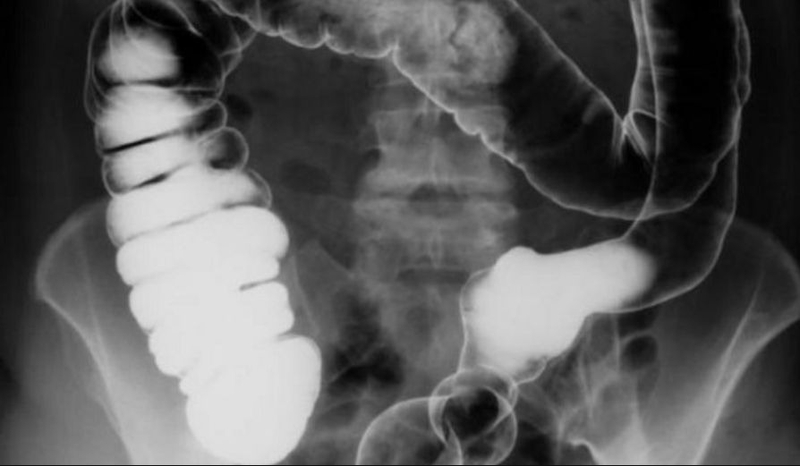

Hình ảnh về giun đũa trong tá tràng, túi mật hoặc các phần của đường mật thường có thể được nhìn thấy thông qua việc chụp X quang hành tá tràng với việc sử dụng thuốc cản quang. Trong các tình huống khẩn cấp, giun trong đường mật có thể được phát hiện thông qua siêu âm, CT hoặc MRI đường mật.